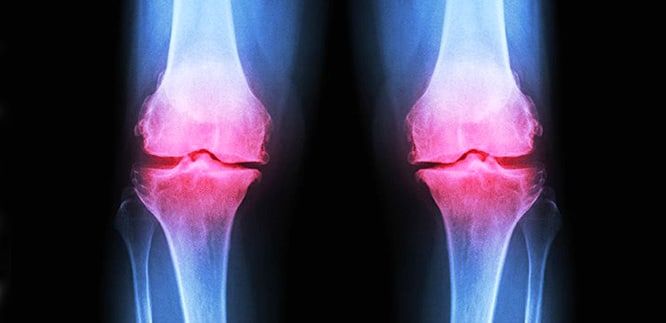

Türkiye, daha önce hiç görülmemiş, sessiz ve acımasız bir salgının pençesinde: İlerleyici Eklem Yıkımı. Milyonlarca insan, her gün hayatını cehenneme çeviren ağrıları "yaşlılığın doğal bir parçası" sanarak kendini kandırıyor. Oysa bu, basit bir ağrı değil; bu, vücudunuzun içinde işleyen, sizi yavaş yavaş yutan bir canavar. Eklem sıvısı kuruyor, kıkırdak zırhı eriyor ve kemikleriniz birbirini yiyerek sizi adım adım tam bir çaresizliğe sürüklüyor. Bu dehşet verici tablo, hayatını insanlığı kurtarmaya adayan dünyaca ünlü cerrah Prof. Dr. Mehmet Öz'ü uykularından etti ve onu bu formülü geliştirmeye mecbur bıraktı.

- Mekanik İflas: Kıkırdak dokusu tamamen yok olur. Artık iki kemik, bir zımpara kağıdı gibi doğrudan birbirine sürter. Bu sadece dayanılmaz bir acı yaratmakla kalmaz, kemiklerde kalıcı deformasyonlara neden olur. Eklem, artık vücudun ağırlığını taşıyamaz.